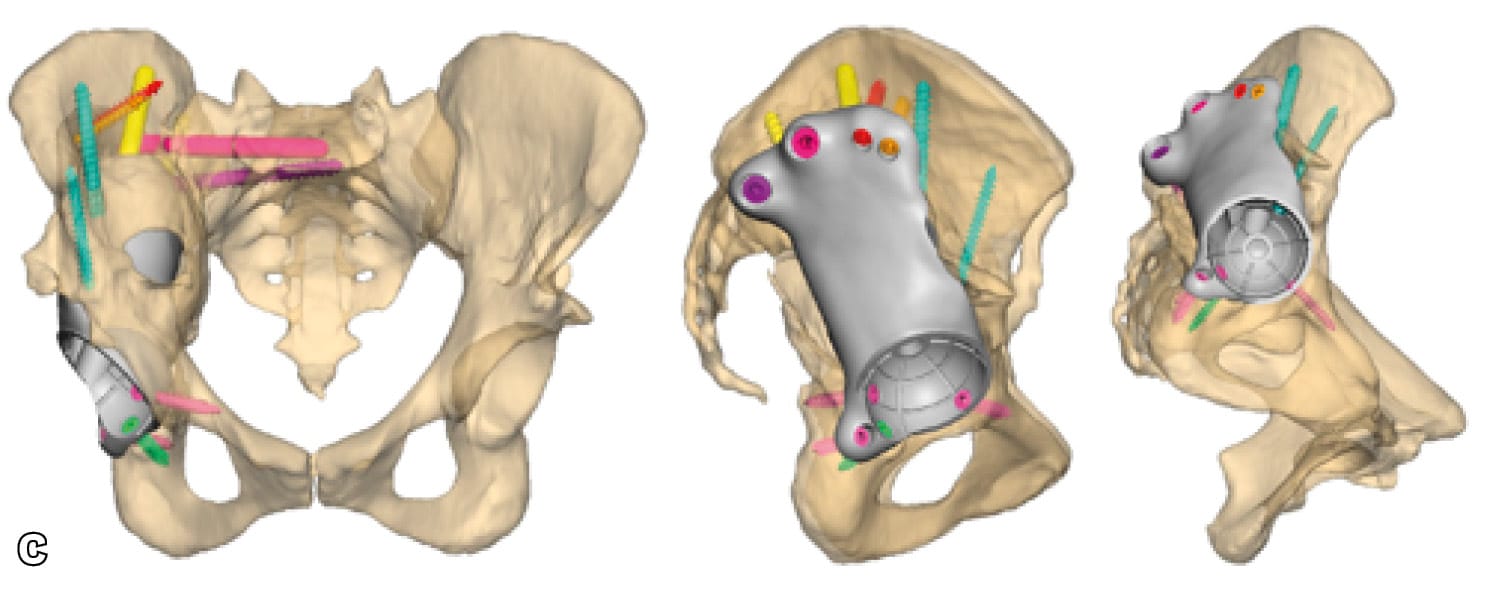

Severe post-operative defects. Principles of management and outcomes of specific patterns are not clearly reported in the literature. Based on the Sen clacification,[1] Sen RK, Mukhopadhyay R, Pattanshetti V, Saini G, Tripathy SK, Sethy SS, Sharma SK. A New Classification System for Acetabular Bone Defect Evaluation in Posttraumatic Acetabular Nonunion and Malunion. Indian J Orthop. 2022 Jun 27;56(9):1601-1612 types 1, 2, 3-A and 5 can be treated with surgical techniques used in revision THA surgery. For severe defects (such as 3-B, 4-A and 4-B), the restoration of hip center of rotation, cup offset, inclination and anterversion and hip stability can be achived only with custom-made implants (Figures 3 and 4).

Triflange and tumour like custom made acetabular impants. Modern technology allows the production of personalised implants for special conditions. These type of implants are custom made, porous coated titanium implants and are considered the last therapeutic salvage option, before excisional arthroplasty, for severe acetabular defects and PD. The implants are designed and manufactured based on pelvic models created by thin-slice pelvic 3-D CT-scans with metal subtraction software (Figures 7 and 8). Early and mid-term outcomes are encouraging but premium cost and length of production time limit their use.[20], DeBoer DK, Christie MJ, Brinson MF, Morrison JC. Revision total hip arthroplasty for pelvic discontinuity. J Bone Joint Surg Am. 2007; 89(4):870-876.[21], Taunton MJ, Ferhing TK, Edwards P, Bersasek T, Holt GE, Christie MJ. Pelvic discontinuity treated with custom triflange component: a reliable option. Clin Orthop Relat res. 2012; 470(2):428-434.[22] Zhang Y, Gao Z, Zhang B, Du Y, Ma H, Tang Y, Liu Y, Zhou Y. The application of custom-made 3D-printed titanium augments designed through surgical simulation for severe bone defects in complex revision total hip arthroplasty. J Orthop Traumatol. 2022; 6:23(1):37.

Concerns for the use of custom made implants are related to the accuracy of the image based technique used for their production, the accuracy of the implant 3D fitting and implantation, the appropriate surgical approach and exposure and the manufacturing and biology of the implant-bone interface.[23], Hothi H, Henckel J, Bergiers S, Di Laura A, Schlueter-Brust K, Hart A. The analysis of defects in custom 3D-printed acetabular cups: A comparative study of commercially available implants from six manufacturers. J Orthop Res. 2023; 41(7):1505-1516.[24], Di Laura A, Henckel J, Wescott R, Hothi H, Hart AJ. The effect of metal artefact on the design of custom 3D printed acetabular implants. 3D Print Med. 2020; 26:6(1):23. [25] Gruber MS, Jesenko M, Burghuber J, Hochreiter J, Ritschl P, Ortmaier R. Functional and radiological outcomes after treatment with custom-made acetabular components in patients with Paprosky type 3 acetabular defects: short-term results. BMC Musculoskelet Disord. 2020; 10:21(1):835.